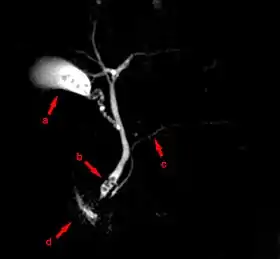

![]() MRCP image showing stones in the distal common bile duct: (a) Gallbladder with stones, (b) Stones in bile duct, (c) Pancreatic duct, (d) Duodenum. | |